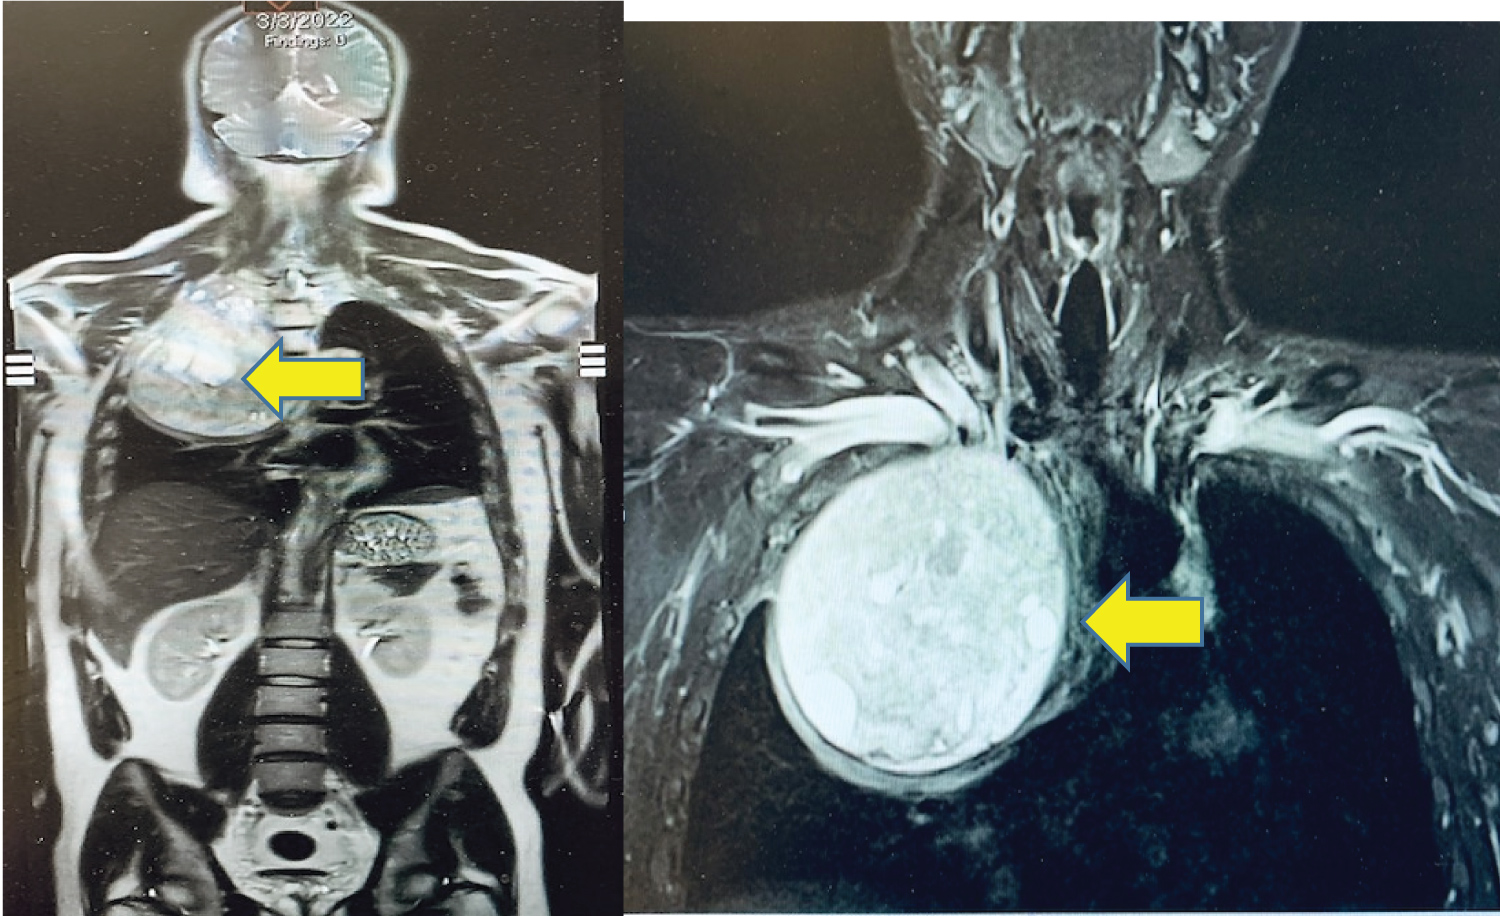

A 33-year-old man presented with right chest and arm pain, right arm sensory and motor deficits along with the ulnar nerve distribution, and right arm anhidrosis. Imaging was remarkable for a 13.4 cm × 12.3 cm heterogeneously enhancing mass from the right 2nd rib growing into the right thoracic inlet and right lung apex. The tumor caused normal lung parenchymal deviation with extensive right-sided neoplastic neuroforaminal involvement and brachial plexus compression (Figure 1). A biopsy of the mass was reported as mesenchymal chondrosarcoma. After chemotherapy and radiation therapy, some of his symptoms, including right arm pain improved and the total tumor volume was slightly reduced. The patient was not taking pain medication at the time he was referred to our hospital for neuro/thoracic surgical consultations for possible tumor resection.

Figure 1: Preoperative Chest MRI image: Heterogeneously enhancing mass (arrows) in the right thoracic inlets and lung apex (13.4 cm × 12.3 cm).